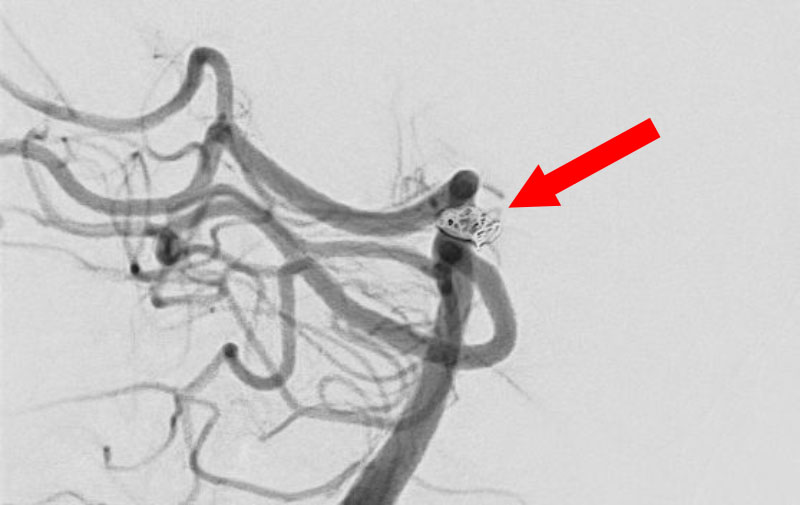

'25年11月

くも膜下出血

右内頚動脈後交通動脈

分岐部動脈瘤破裂

60代

救急外来

No.1593 手術前

No.1593 手術中

No.1593 手術後